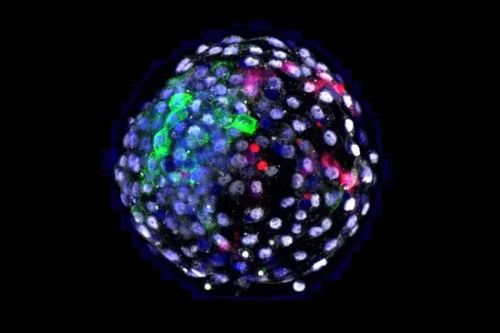

Фото: Weizhi Ji/Kunming University of Science and Technology Филадельфия, 22 апреля. Католические теологи и специалисты по биоэтике обеспокоены сообщениями о том, что ученые успешно создали «химерный эмбрион», часть клеточного материала которого заимствована у макаки, а часть у человека, сообщает «Седмица» со ссылкой на catholicnewsagency. В статье, опубликованной в журнале Cell за 15 апреля, повествуется, что ученые взяли бластоцисту* у макаки и внедрили в нее человеческие клетки. Затем бластоциста успешно развилась в химерный эмбрион из биоматериала обоих видов. Цель эксперимента состоит в том, чтобы использовать биологические материалы приматов для выращивания органов, пригодных для трансплантации людям. Подобные эксперименты уже ставились над животными, однако это первый случай создания химеры обезьяночеловека. «Когда мы рассматриваем этические аспекты смешения клеточных культур человека и животных для получения «химерных созданий», первостепенное значение приобретают детали вмешательства, производимого исследователями, - заявил в интервью изданию CNA священник Тад Пахолчик (Tad Pacholczyk), директор службы образования Национального центра по католической биоэтике (National Catholic Bioethics Center) в Филадельфии (штат Пенсильвания, США). – Этическая суть этого исследования заключается в имплантации человеческих стволовых клеток в эмбрионы обезьяны, чтобы вырастить человеческие сердца, почки и другие органы внутри животного – обезьяны в данном случае; и тем самым отчасти справиться с серьезной нехваткой человеческих донорских органов для трансплантации. Такие эксперименты можно считать этичными только при условии соблюдения определенных пределов и границ. К примеру, обратный эксперимент – с внедрением обезьяньих стволовых клеток человеку – вызывает серьезные этические возражения». Как подчеркнул о. Тад Пахольчик, основная этическая граница, за которую нельзя переходить при экспериментах такого рода, определяется их целью. «Главная цель в данном случае состоит в том, чтобы побудить обезьяну вырастить орган или ткань другого вида, а не создать новый вид живых существ. Подобные процедуры не должны ставить цель репликации основ человеческой идентичности или человеческого сознания в обезьяне – например, через вмешательство в механизмы формирования человеческого мозга, – указал католический философ. – При этом обезьяну нельзя наделять рядом способностей – к примеру, способностью воспроизводить человеческие гаметы**». *«зачаток» (греч.), ранняя форма зародыша в видешара размером 0.1мм и меньше, состоящего из нескольких десятков или сотен клеток **половые или репродуктивные клетки, имеющие гаплоидный (одинарный) набор хромосом